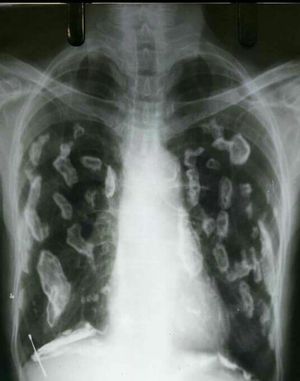

HOLLY LEAF SIGN

This condition refers to the appearance of PLEURAL PLAQUES on chest x-rays. Their irregular thickened nodular edges are likened to the appearance of a holly leaf.